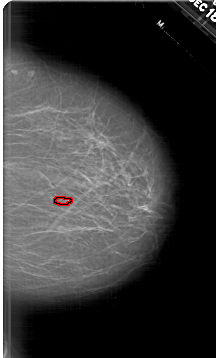

A_1633_1.RIGHT_MLO

LEFT_MLO LINES 6256 PIXELS_PER_LINE 4576 BITS_PER_PIXEL 12 RESOLUTION 43.5 NON_OVERLAY

FILE: A_1633_1.RIGHT_MLO.OVERLAY

TOTAL_ABNORMALITIES 1

ABNORMALITY 1

LESION_TYPE CALCIFICATION TYPE PLEOMORPHIC DISTRIBUTION CLUSTERED

ASSESSMENT 4

SUBTLETY 3

PATHOLOGY BENIGN

TOTAL_OUTLINES 1

BOUNDARY